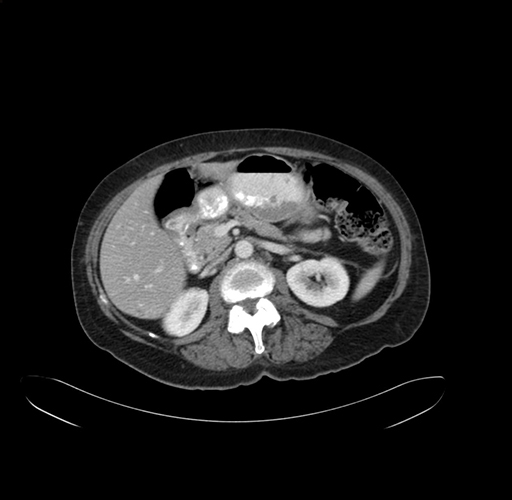

Pre-Chemo: Axial Venous

Axial Venous